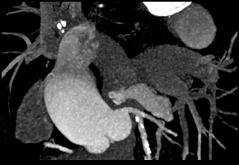

上面一组图像考虑为 ( )A、左前降支钙化B、左旋支钙化C、正常的左前降支D、右侧冠状动脉钙化E、正常的右侧冠状动脉

问题 上面一组图像考虑为 ( )

选项 A、左前降支钙化 B、左旋支钙化 C、正常的左前降支 D、右侧冠状动脉钙化 E、正常的右侧冠状动脉

答案 A